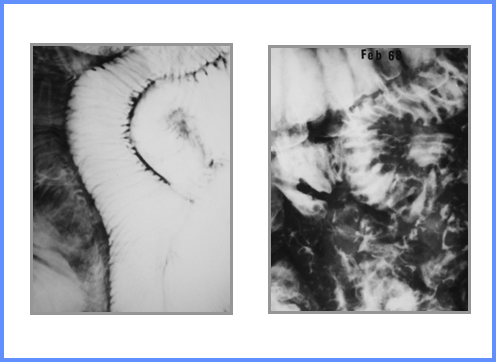

Stack-of-coins

Picket fence